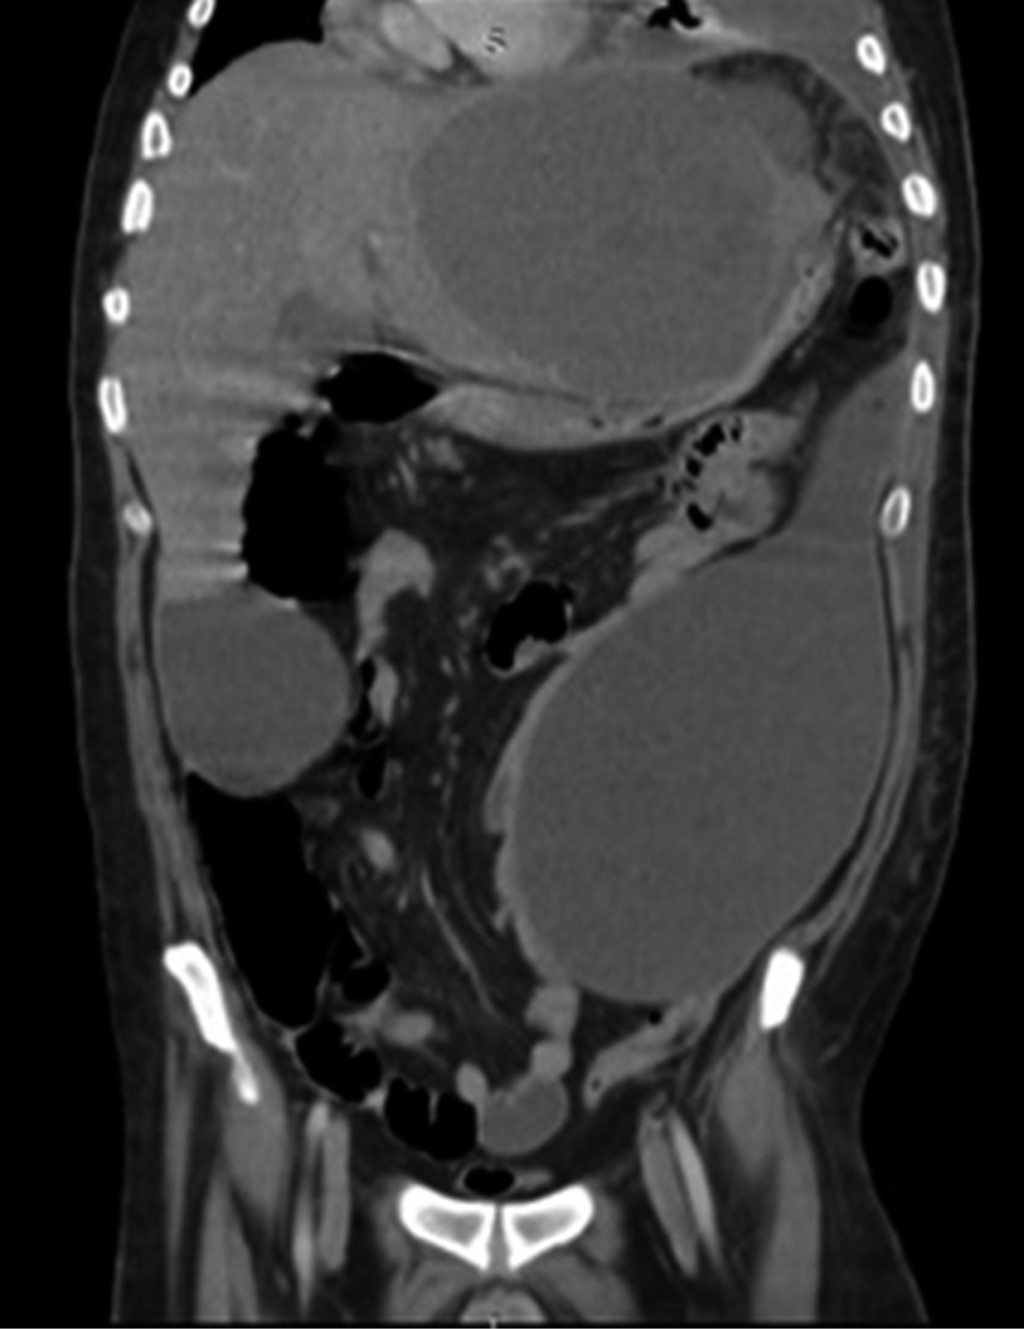

An anteroposterior (AP) chest X-ray was performed, in which a left pleural effusion covering more than 50% was visualized. A computed tomography scan showed a significant amount of fluid in the left pleural space that conditioned a passive atelectasis of the lower lobe (Figure 1); the liver was found with heterogeneous density with an increase of the left hepatic lobe secondary to the presence of a heterogeneous hypodense lesion with lobulated borders, showing peripheral reinforcement and some internal septa covering segments II, III, IVa, and IVb measuring approximately 20 × 14.5 × 12.5 cm (Figure 2), conditioning posterior displacement and compression of the stomach and pancreas and caudal displacement of the intestinal loops (Figures 3 and 4). In the lower pole of the right hepatic lobe adjacent to segment IV, a homogeneous cystic lesion with peripheral enhancement was identified after intravenous contrast administration, measuring 25 × 27 × 13 cm in its major axes. A Foley tube and nasogastric tube were placed as initial management draining a liquid of gastric characteristics (30 ml). A central catheter was placed and verified by radiography. Imaging studies were requested. Fasting was ordered and fluid therapy, antibiotic therapy with ceftriaxone and metronidazole, pain management, glycemic control, and gastric protection were started. When visualizing the image of the left pleural effusion, it was decided to perform a thoracentesis, obtaining a thick exudate with a chocolate appearance. When the tomography was available, urgent surgical treatment was performed.

Figure 1